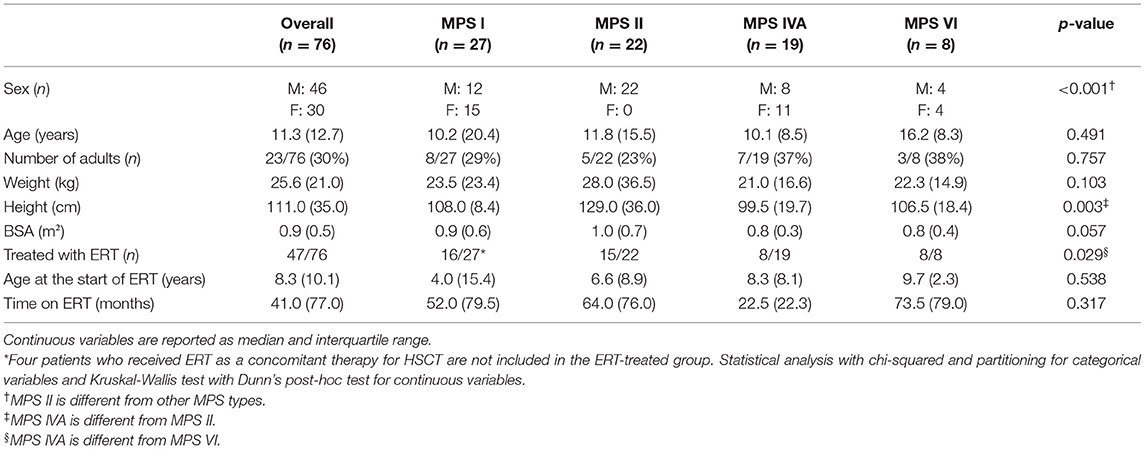

A total of 76 patients (27 MPS I, 22 MPS II, 19 MPS IVA, and 8 MPS VI), 46 males and 30 females, with a mean age of 14.2 years, being 53 children and 23 adults, were included in this study (Tables 1, 2). Most of those patients were analyzed in a previous publication, which focused on the aortic root dimension (16). All MPS II patients were males. MPS IVA patients had a lower median height, when compared to MPS II patients and were less frequently treated with ERT when compared to MPS VI patients.

Valvular Disease

Among the 76 patients included in this study, left side valvular disease was a frequent finding, with mitral and aortic thickening being reported in most patients in all four MPS types (Figure 1). Furthermore, mitral and aortic insufficiency, mostly mild, were frequently found in patients with MPS I, II, and VI, but were also observed in a significant proportion of patients with MPS IVA. To a lesser extent, tricuspid valve thickening and insufficiency were also present in patients with MPS types I, II, and VI. Heart valve involvement was both more prevalent and more severe in adult patients (Figure 2; Table 3).

Figure 1. Prevalence of heart valve abnormalities in MPS types I, II, IVA, and VI, including both treated and untreated subjects.

In this study, we assessed the prevalence of cardiac manifestations in a cohort of patients with MPS I, II, IVA, and VI; which included mostly patients treated with ERT. In agreement with previous reports (3, 17–20), valve involvement comprised mainly left-sided valves and affected a high proportion of patients. Mitral valve involvement was more common than the aortic valve in the four MPS types. Valve involvement, especially aortic insufficiency and mitral stenosis, was more commonly observed in older patients. We could not identify any significant worsening or improvement of valve pathology after ERT. It is widely accepted that ERT has limited impact on valve abnormalities of patients with MPS (13, 21–25), probably due to poor tissue penetration and irreversibility of the valvar damage. Nevertheless, it may have a role in preventing or delaying its appearance when treatment is started very early, as suggested by studies with sibling pairs and animal models (26, 27).